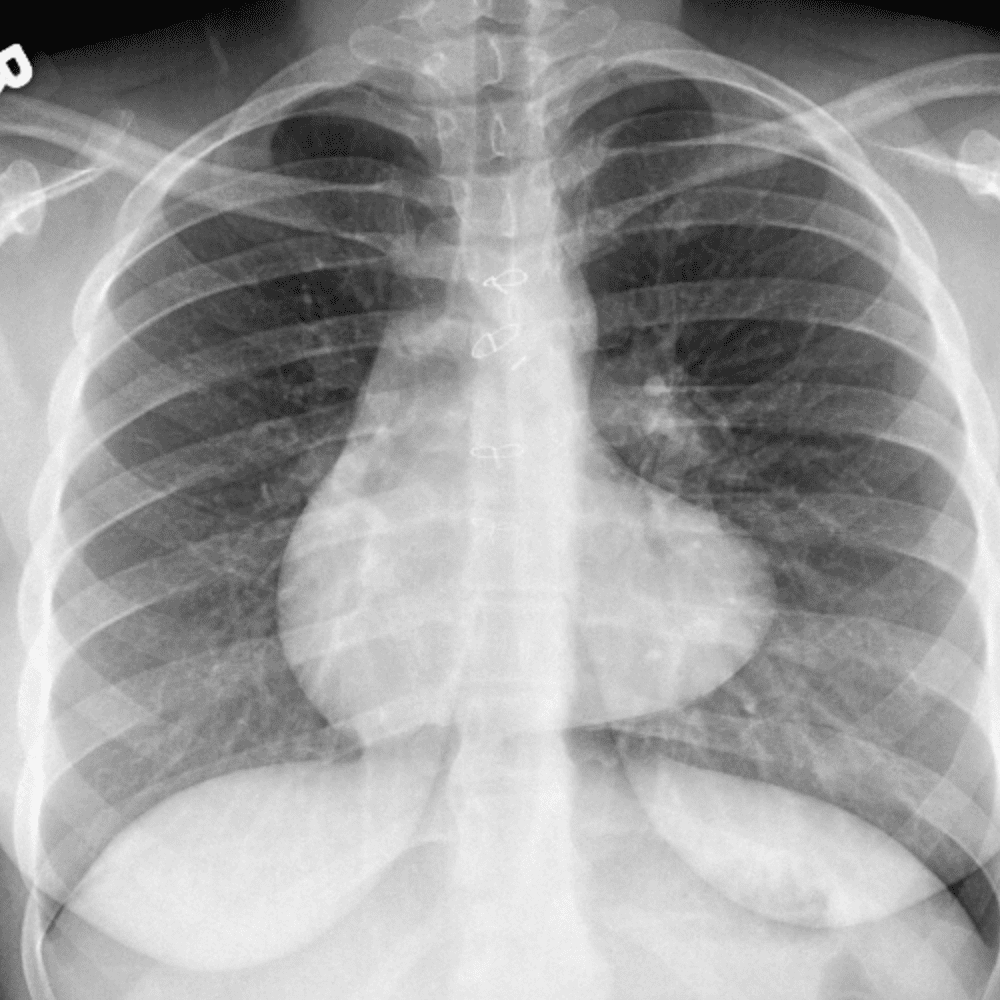

Peds Chest

Practice

Simulates call by including subtle or difficult cases and some normals.

50 cases